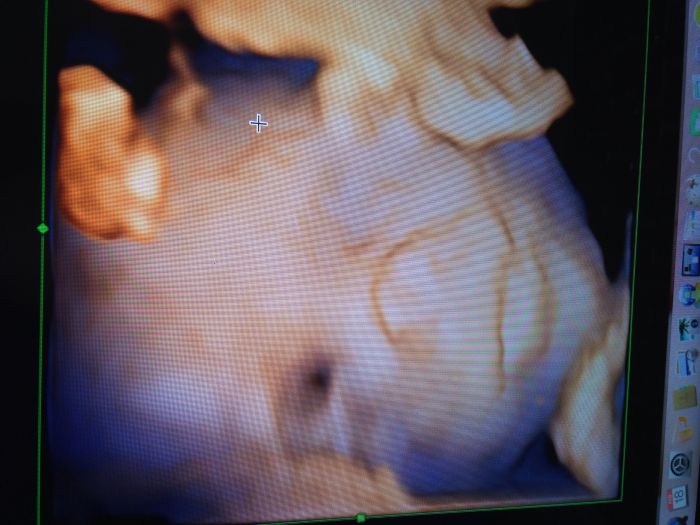

Já mám kontrolu zitra u mojí dr.a v pondělí v prenatalu velký UZ.už se těším!!!a chci si nechat potvrdit pohlaví,tak jsem zvědavá,jestli je to pořád kluk nebo uvidí holčičku